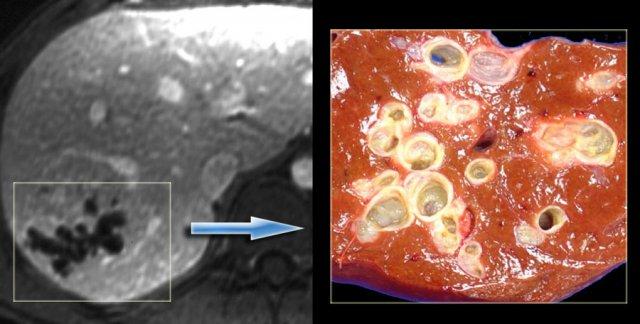

Trong một số trường hợp bệnh Caroli, các dấu hiệu hình ảnh có thể mô phỏng u nang tân sinh như trong trường hợp bên trái.

Trường hợp này ban đầu được chẩn đoán là u nang tuyến đường mật.

Tuy nhiên, bệnh phẩm đại thể cho thấy các ống mật giãn và dị dạng tấm ống dẫn được xác nhận trên vi thể.